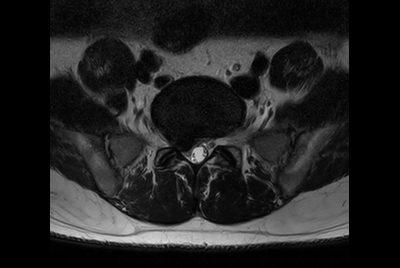

Compressed SENSE Prostate imaging

-

Prostate with dS ZOOM imaging

-

High resolution Prostate imaging with Compressed SENSE

-

Prostate lesion with fat-free mDIXON XD imaging

-

Prostate lesion with high b-value DWI

-

Prostate imaging with motion reduction techniques

-

Prostate with Compressed SENSE on BlueSeal magnet

-